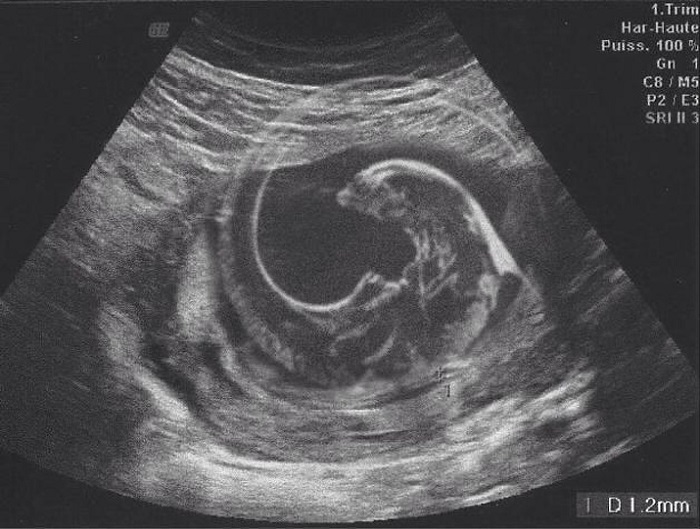

12. A gyermekünkről készült ultrahang képet az én e-mail címemre küldték át a vizsgálat után. Mielőtt átküldtem volna a feleségemnek, poénból rászerkesztettem egy alient a képre. A feleségemnek nem tűnt fel, hogy valami nem stimmel a képpel, ezért tovább küldte az összes rokonunknak.